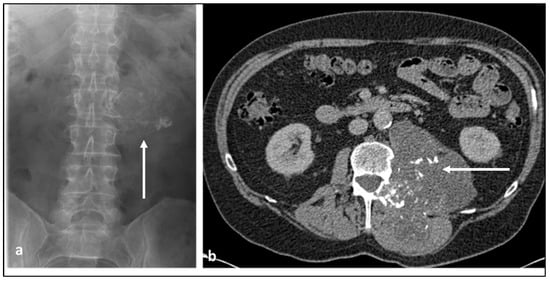

| Chondrosarcoma | Lytic lesion. ‘Rings and arcs’ calcification characteristic of chondroid matrix. | High T2 signal due to cartilage and myxoid content. Peripheral and septal enhancement. Enhancing extra-osseous soft tissue component. |